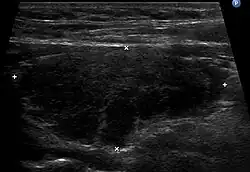

Ultrasound imaging of the thyroid gland (right lobe longitudinal) in a person with Hashimoto thyroiditis

Ultrasound imaging of the thyroid showing Hashimoto's thyroiditis

An ultrasound may be useful in detecting Hashimoto thyroiditis, especially in those with seronegative thyroiditis,[13] or when patients have normal laboratory values but symptoms of autoimmune thyroiditis.[47] Key features detected in the ultrasound of a person with Hashimoto's thyroiditis include "echogenicity, heterogeneity, hypervascularity, and presence of small cysts."[13] Images obtained with ultrasound can evaluate the size of the thyroid, reveal the presence of nodules, or provide clues to the diagnosis of other thyroid conditions.[47]